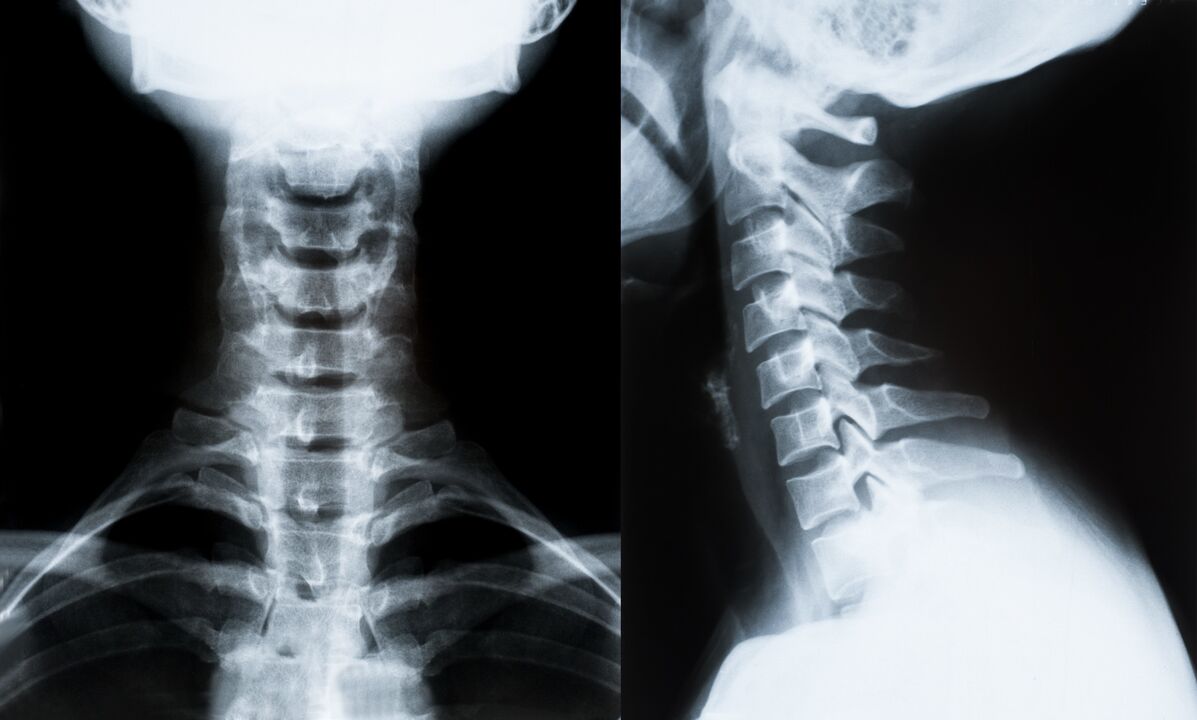

I principali metodi di diagnosi e ulteriore determinazione del trattamento per l'osteocondrosi del rachide cervicale:

- Raggi X. Il metodo diagnostico meno efficace, ma tradizionale.

- La risonanza magnetica è il metodo diagnostico più efficace. Con questo tipo di esame del paziente sono visibili tutte le strutture necessarie.

- Se è necessario misurare i cambiamenti, viene utilizzata la tomografia computerizzata. Determina la presenza di ernie e altre cose.

- L'ultimo metodo è la scansione duplex ad ultrasuoni. Questo metodo di ricerca determina la velocità del flusso sanguigno nelle arterie.

È impossibile determinare con precisione la malattia spinale a casa.